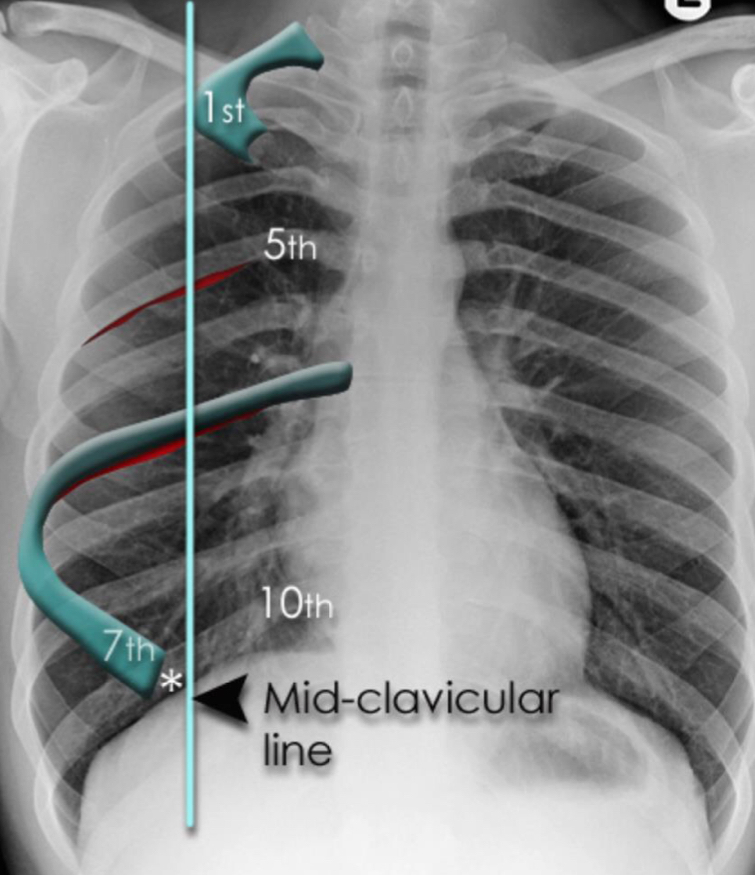

What are the different lung zones on a chest x-ray?

What fissure can you see on a chest x ray?

Horizontal in the right lung running towards right hilum

What might be the pathology if the 1st rib is not visible on chest x ray?

Pancoast tumour as it erodes the first rib